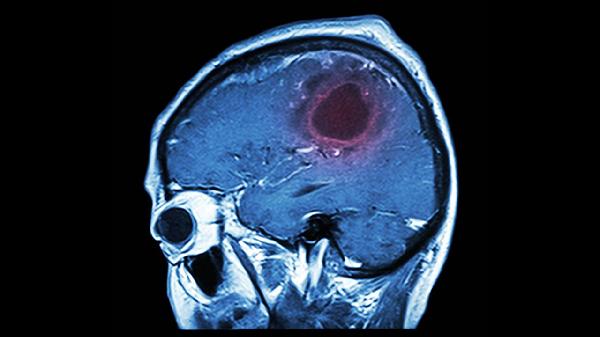

年轻人为何也会发生脑溢血

年轻人发生脑溢血可能与遗传因素、高血压、脑血管结构异常、外伤以及不良生活方式有关。这种疾病通常表现为突然的剧烈头痛、呕吐、肢体无力等,确诊一般需要借助CT或MRI检查,治疗手段包括使用降压药物、手术清除血块以及后期的康复训练。

先天性的动静脉畸形或海绵状血管瘤在年轻时期可能首次破裂,这些异常的血管团容易受到血流冲击而渗血。很多患者在发病前没有任何征兆,一旦发作会出现剧烈头痛并伴有意识障碍,需尽快做DSA检查。治疗方式包括伽玛刀放射治疗或开颅手术,术后常使用甘露醇注射液来降低颅内压力。